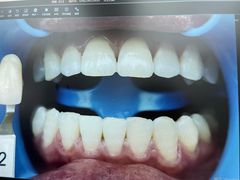

• -牙博士口腔品牌连锁(杨浦店)

CoeY.Sept.4 | 24-06-29

报错